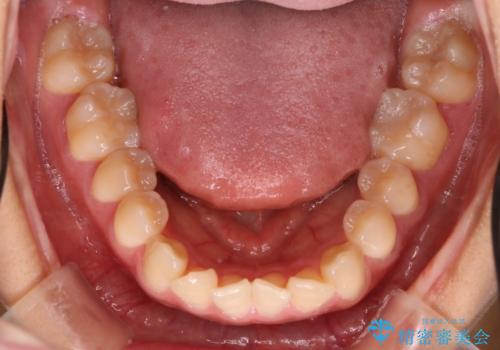

抜かない矯正 審美装置によるワイヤー治療

- 前歯のガタガタを主訴に来院されました。

装着時間に不安がある人は、ワイヤー矯正をおすすめしております。短期間で治療でき患者様にも満足していただきました。